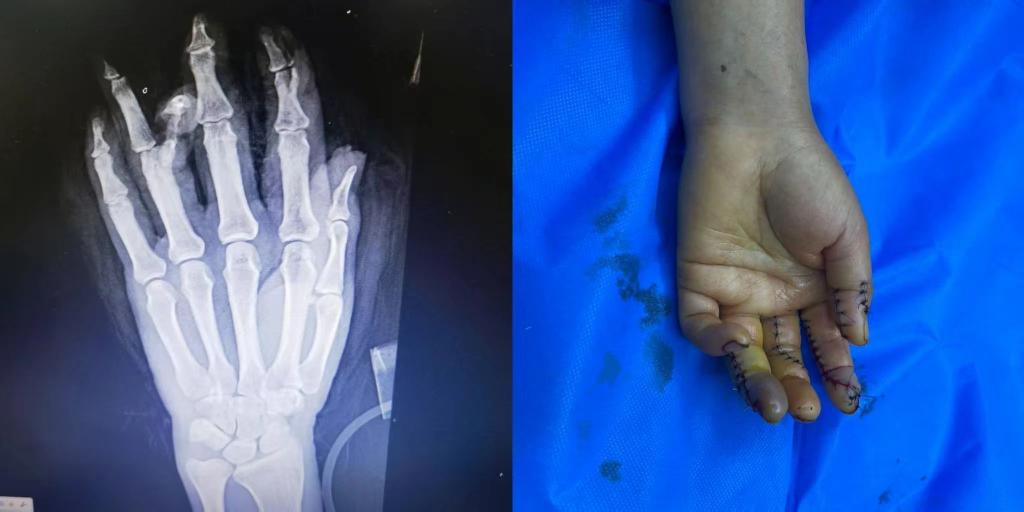

5月1日下午15点30分,新疆医科大学第五临床医学院2020级临床医学班的学生小马(化名)接到了来自伊犁亲戚的电话。电话中得知,亲戚在工作中不幸遭遇意外,左手被机器压伤,导致拇指、食指、中指、无名指均受到不同程度的损伤,受伤最严重的是食指和无名指,竖向劈开了骨头。由于多指多段离断的严重毁损伤,手术难度很大,当地医院的条件有限,为保住患者手指,需要申请前往上级医疗机构治疗。

随后,患者被送入手术室,由李华医生主刀,进行了长达7个小时的断指再植手术。

术后患者损伤严重的手恢复了基本形态,手指末梢血液循环逐步恢复。目前患者的情况基本平稳,在医院等待进一步观察和恢复。